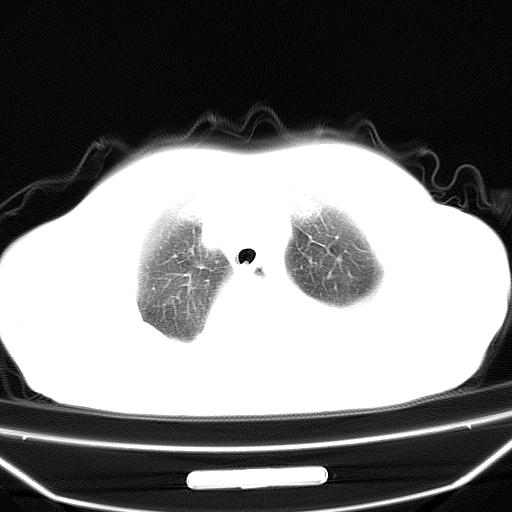

以下是引用jiangjing在2008-4-20 10:43:00的发言:[br]结合病史支持 冠心病[冠状动脉钙化],心功能不全,肺淤血、肺水肿,双侧胸腔与斜裂积液

以下是引用liuyue在2008-4-19 22:25:00的发言:[br]先考虑:1.心衰伴肺水肿、双侧胸腔积液、叶间积液、双下肺不完全性肺不张; [br] 2.冠状动脉粥样硬化。